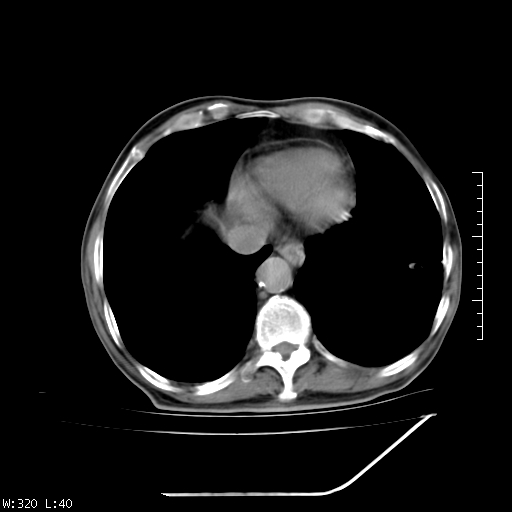

标题: CT23994:男、72、咳嗽、气短两月余,近来消瘦。 [打印本页]

标题: CT23994:男、72、咳嗽、气短两月余,近来消瘦。

右上肺实变,与胸膜关系密切,右肺容积缩小,隆突下淋巴结增大,考虑1 肺结核 2 肺癌

右上肺大片状密度增高影,与胸膜关系密切,内见低密度透亮影,胸膜下可见三角形不张影,左下肺沿支气管走形结节影,纵膈内淋巴结显示。考虑结核并疤痕性不张可能性大,建议穿刺活检,排除肺泡癌。